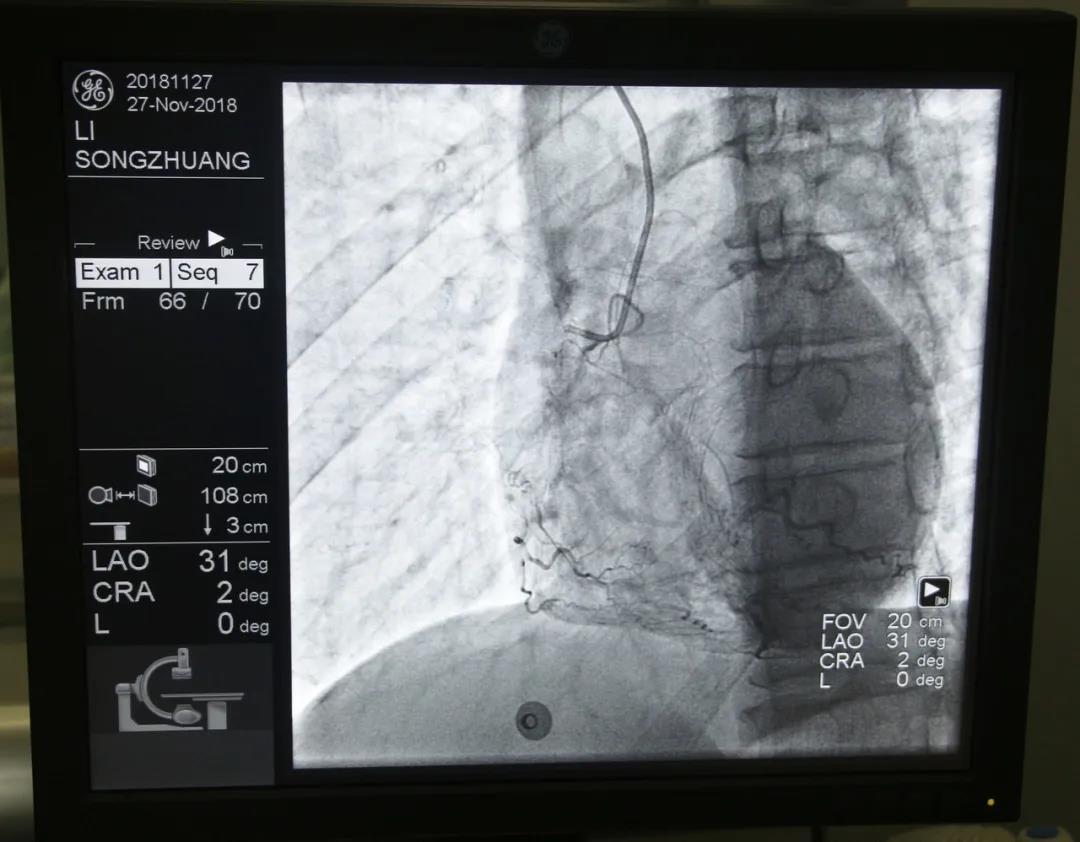

心內(nèi)科醫(yī)務(wù)人員冠狀動脈造影中

“冠狀動脈造影”即“冠脈造影”,是診斷冠心病的一種常用方法,作為一種有創(chuàng)診斷技術(shù),它被稱為診斷冠心病的“金標(biāo)準(zhǔn)”。心內(nèi)科融無創(chuàng)與有創(chuàng)協(xié)同治療為一體,硬件設(shè)施齊全,配有美國GE大C型臂數(shù)字減影X線造影機(jī),心臟臨時(shí)起搏器、床旁監(jiān)護(hù)儀、除顫儀、自動分析心電圖等,設(shè)有心臟重癥監(jiān)護(hù)室(CCU),擁有1個(gè)獨(dú)立導(dǎo)管室,設(shè)有心內(nèi)科??崎T診、心內(nèi)科病房(現(xiàn)有床位71張)、心血管無創(chuàng)檢查室、心電圖室等部門。科室現(xiàn)已熟練開展冠狀動脈造影技術(shù),為心血管疾病患者帶來了福音。